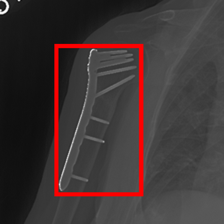

MURA Musculoskeletal Radiograph Dataset – Obtained from 14,863 bone X-ray studies, Stanford’s MURA dataset involves the identification of abnormalities such as bone fractures and hardware implants [21].

Using the trained models with state-of-the-art performance, we follow the protocol detailed in Section 2.4 and present experimental results on interpretability in Figure 3, Figure 4, and Table 3. In particular, Figure 3 illustrates several qualitative examples, while Table 3 displays pointing game accuracy and mean IoU scores. Finally, Figure 4 represents IoU distributions represented in the form of boxplots. Based on these results, we make the observations below.

Qualitative results can be misleading. In Figure 3, we present qualitative interpretability outputs for all methods considered. As can be seen, depending on the selected subset of images and the method, both accurate and inaccurate interpretability maps can be found. These findings emphasize the danger of making strong claims about interpretability methods based solely on qualitative results, including attention maps.

Bounding box annotations may be inadequate for interpretability evaluation on medical datasets. In this work, we worked with expert clinicians to highlight disease-positive regions with a bounding box to evaluate the efficacy of interpretability maps. However, we discover that this approach comes with significant shortcomings. For instance, in the MURA and Kvasir datasets, regions of interest often occupy large spaces, resulting in annotation boxes that include non-target areas, and leading to inflated results regardless of the method’s actual precision. Therefore, using segmentation maps, which provide detailed pixel-level annotations of the areas of interest, could offer a more precise evaluation in future research.